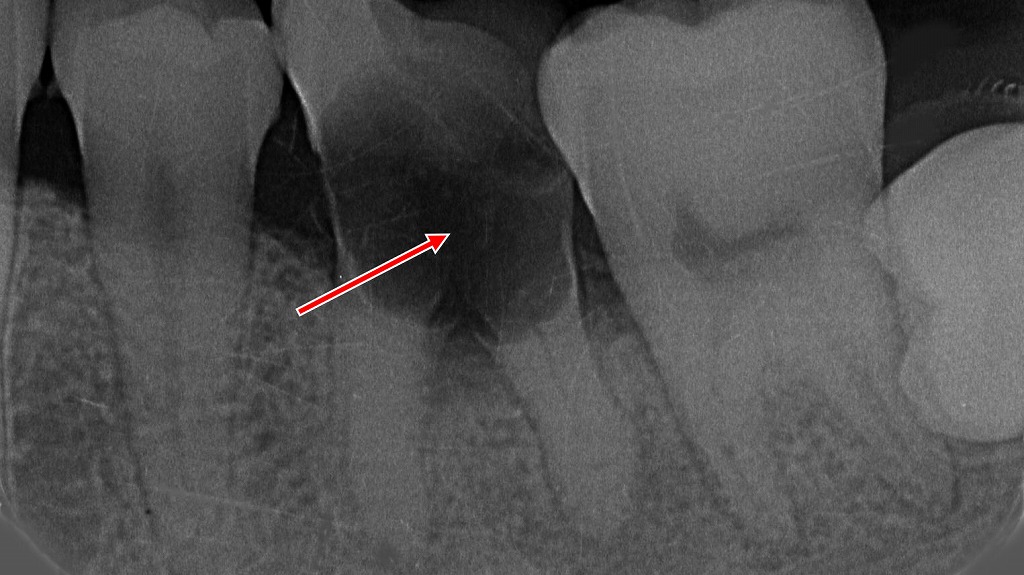

虫歯による穴:症例2

この画像は、下顎の歯列を咬合面(上から)撮影した口腔内写真です。

🔍 解説

赤い矢印で示されているのは右下第2小臼歯(5番)です。

歯の近心側(手前側の面)に、小さな黒い穴が確認されます。これは虫歯(う蝕)によって形成された穴です。

🦷 詳細説明

- 虫歯は歯の表面(エナメル質)から始まり、象牙質へと進行します。

- この段階では穴が浅く、痛みが出にくいこともありますが、放置すると進行して大きくなり、冷たいものがしみたり、神経(歯髄)にまで達するおそれがあります。

- 写真のように、清掃が難しい部位では虫歯が発生しやすくなります。

💡 ポイント

このような小さな虫歯は、早期に発見して治療することで、最小限の削除で済みます。定期的な検診とレントゲン撮影により、見えにくい部位の虫歯も早期発見が可能です。